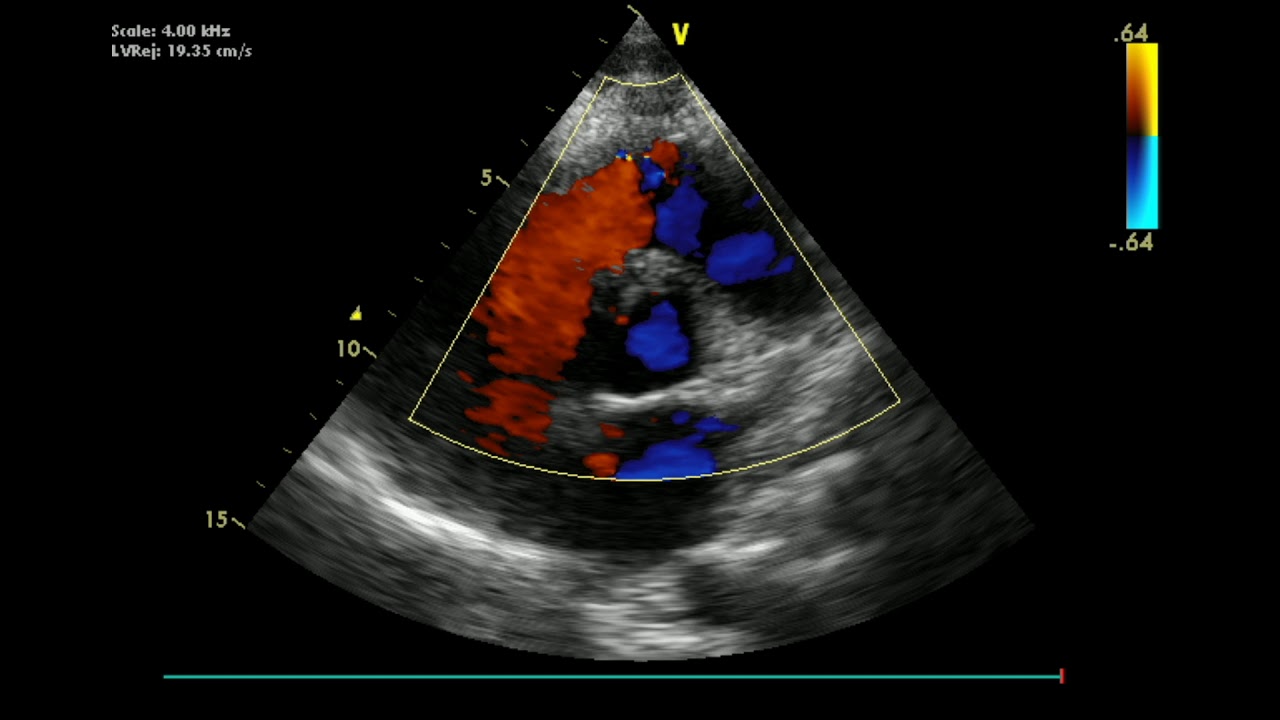

Узи дмжп

Узи дмжп 115 фотографий